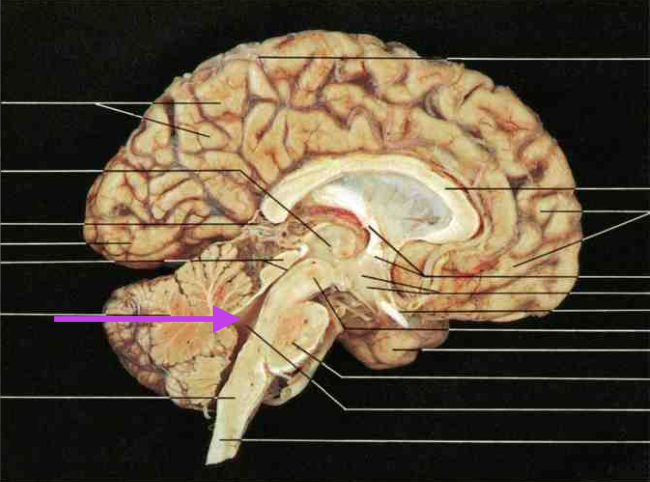

Midbrain. Section is Brain Stem.

Cerebral Aqueduct. Part of Midbrain. Section is brain stem.

Inferior Colliculus. Part of the midbrain. Section is brain stem.

Superior colliculus. Part of midbrain. section is brain stem.

Pons. Section is brain stem.

Medulla oblongata. Section is brain stem.

Fourth ventricle. Section is brain stem.

Cerebellum